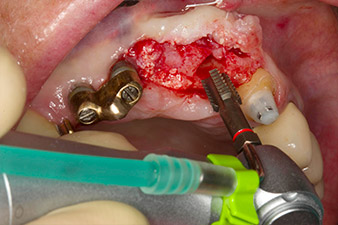

Dopo la prima guarigione, i tessuti molli sono stati sagomati con un ponte rivestito nella porzione basale. Due mesi dopo, il sito è stato esposto con una leggera incisione sula cresta palatoalveolare (Fig. 2). Si è visto che le dimensioni dell'osso alveolare erano sufficienti in corrispondenza della posizione 22. Le figure 2 e 4 mostrano la preparazione della sede di impianto, l'avvitamento e l'impianto utilizzando Implantmed.

Per compensare la perdita ossea periodontale e ottenere un risultato estetico piacevole, si è proceduto all'impianto unitamente alla rigenerazione guidata dell'osso (tecnica GBR) con materiale di riempimento xenogenico e membrana di collagene (Fig. 5 e 6).